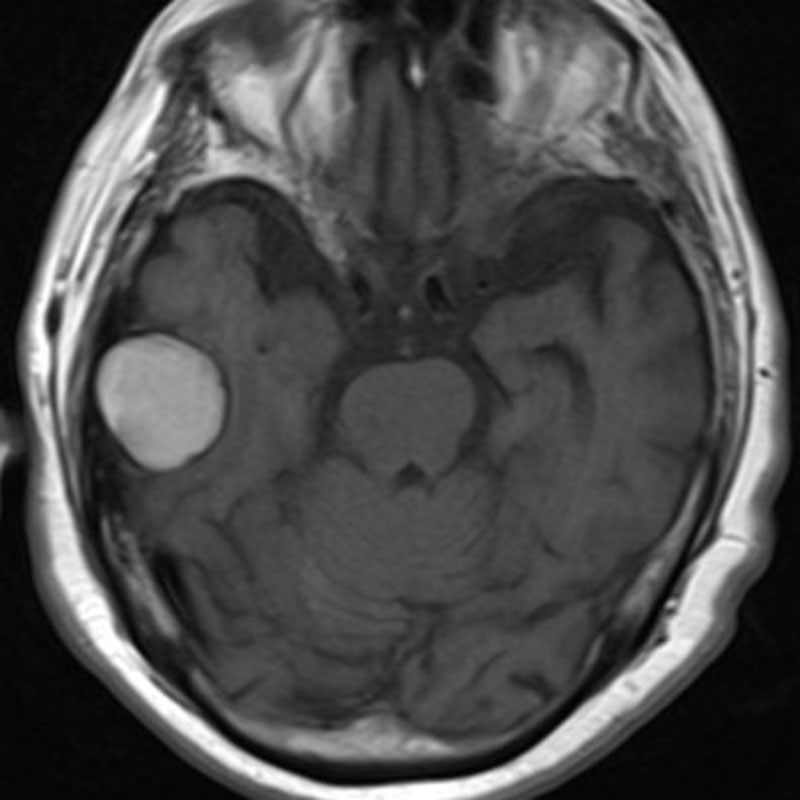

脳動静脈奇形

血管塞栓術

松田/濵田/元永